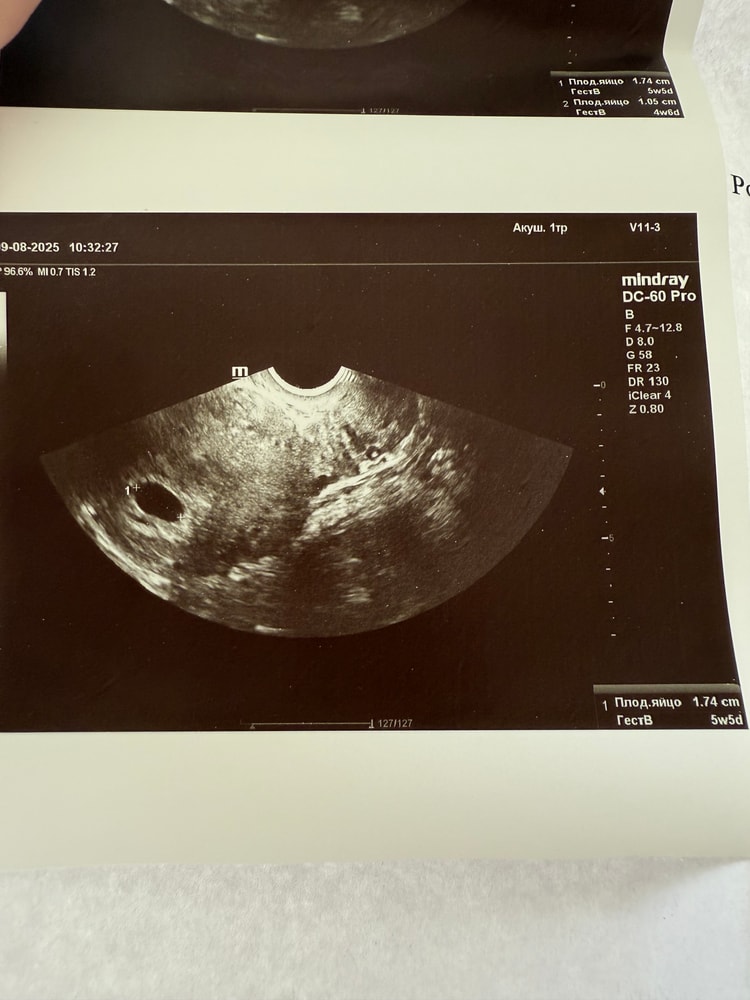

Обследования, узи, анализыДевочки, наверное рано я обрадовалась🥺 сходила на узи по месячным срок 6,6 недель. На узи только пя пустое с прошлого узи подросло но сроку не соответствует на 7 дней ( сказали подождать 2 недели и снова на узи, но не знаю есть ли смысл? У кого нибудь было так что на 7 неделе не было эмбриона? Расстроена слов нет.

Буду трижды мамой в этом году, пя 1,74 см соответствует 5,5 недель жм на первом узи был сейчас не увидели.